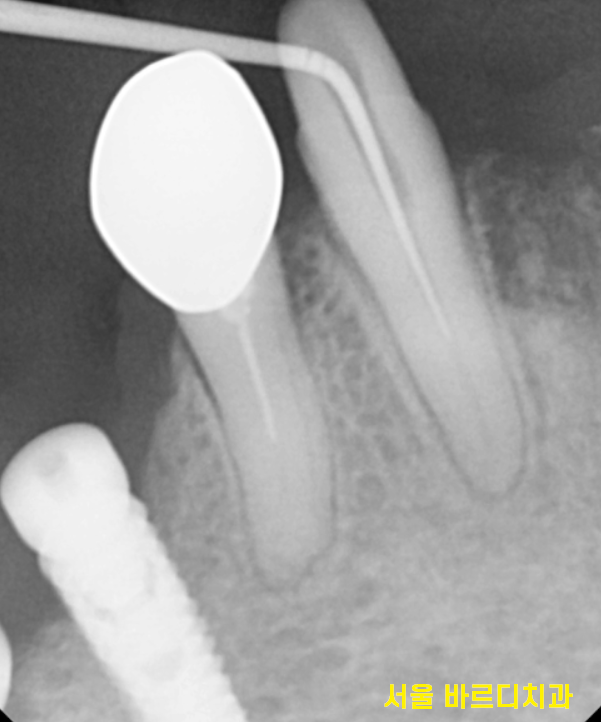

다수의 치아 상실

치아가 많이 상실된 상태였습니다.

그동안 길동 치과에서는

살릴 수 있는 치아를 치료하며

환자분의 의견을 기다렸습니다.